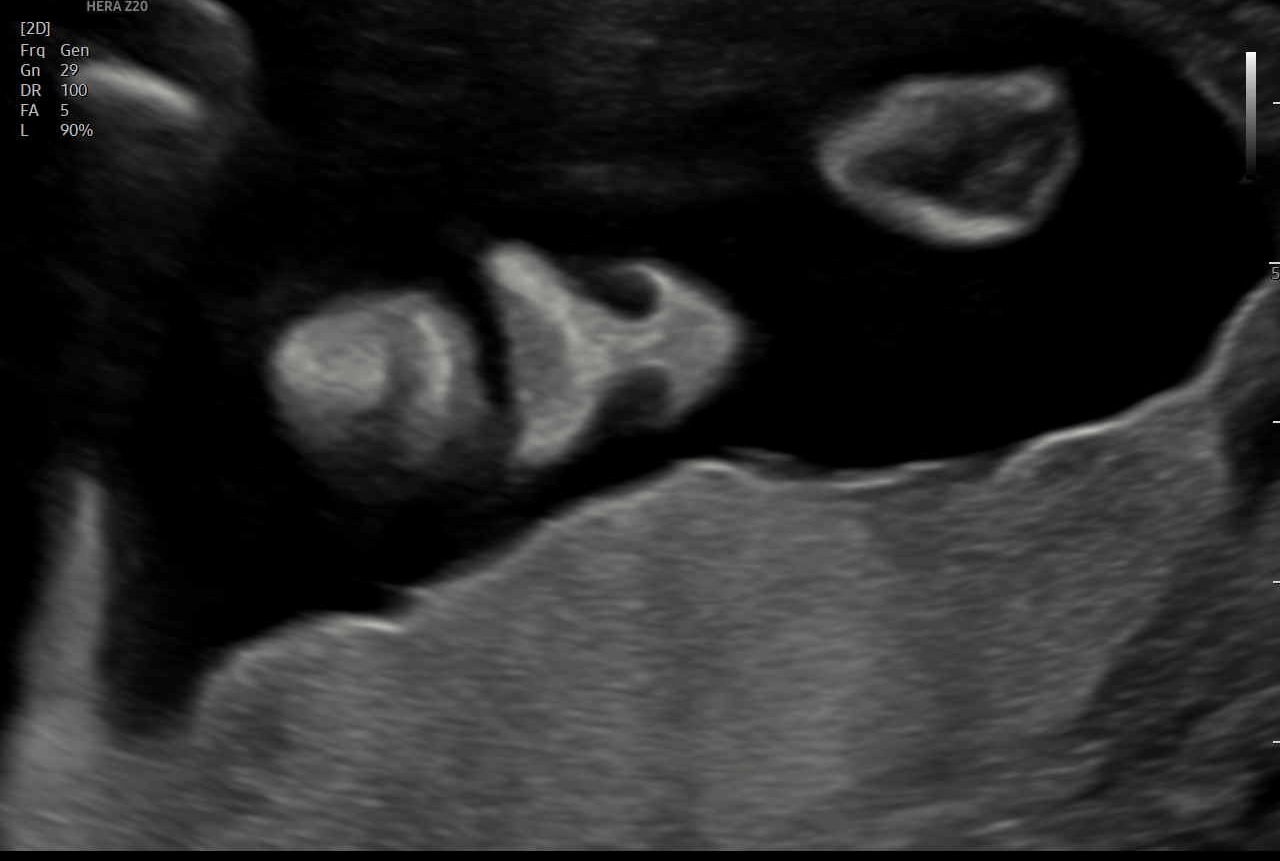

„Feindiagnostik“: 20-24 SSW

Wir schauen Ihr Kind im Ultraschall detailliert von Kopf bis Fuß an. Mit Fortschreiten der Schwangerschaft liegt der Fokus hier besonders auf der Entwicklung von Herz und Kopf Ihres Kindes. So können wir Besonderheiten frühzeitig erkennen, die Schwangerschaft optimal begleiten und die Geburt bestmöglich vorbereiten. In manchen Fällen ist eine Behandlung bereits während der Schwangerschaft möglich.